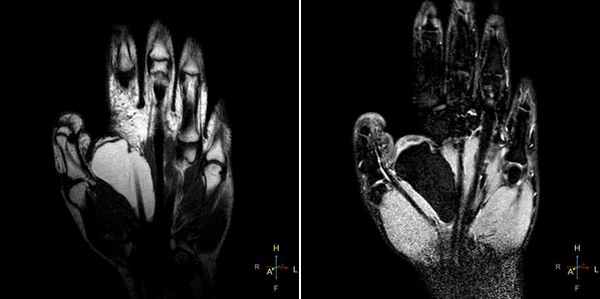

(Слева) Рентгенография левого лучезапястного сустава в ПЗ проекции: повышение плотности полулунной костив. Нет потери высоты и фрагментации. Признаки соответствуют II стадии болезни Кинбека.

(Справа) Фронтальная Т1ВИ МР-И: неоднородный гипоинтенсивный до темного сигнал в полулунной кости. Темный сигнал соответствует склерозу/фиброзу при прогрессировании заболевания. Структурные изменения визуализируются и на других изображениях, что указывают на III стадию болезни Кинбека. (Слева) Рентгенография в ЗП проекции: неоднородный склероз полулунной кости со значительным коллапсом проксимальной суставной поверхности. Несмотря на выраженные изменения, было выполнено укорочение лучевой кости. Операция выполнена для коррекции отрицательного локтелучевого индекса в попытке уменьшения механической нагрузки на деформированную полулунную кость.

(Справа) Рентгенография в ЗП проекции, этот же пациент после лечения по поводу хронического болевого синдрома. Полулунная кость была резицирована и выполнен ограниченный (головчато-крючковидный) остеосинтез. (Слева) Фронтальная Т2ВИ FS МР-И: I стадия болезни Кинбека. Отрицательный локтелучевой индекс. Отек костного мозга в полулунной и головчатой костях. Отек головчатой кости возможен на фоне нарушения осевой механической нагрузки вследствие короткой локтевой кости.

(Справа) Фронтальная T1 ВИ МР-И, этот же пациент: отек костного мозга в полулунной кости. Главная ось нагрузки проходит от лучевой кости к полулунной и головчатой до среднего пальца, ее легко оценить. Нормальная рентгенологическая картина говорит о I стадии маляции полулунной кости.